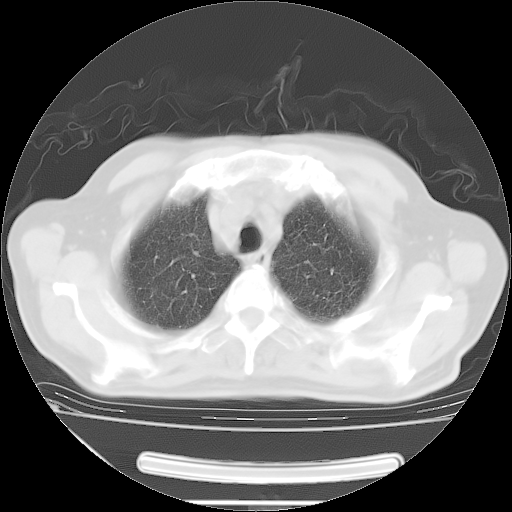

今天复查肺部CT,发现双肺广泛磨玻璃样改变。所以我把3月19日和5月9日相隔50天的肺部CT上传。请大家会诊。

2009年3月19日肺部CT片。

2009年3月19日肺部CT

大致读了系列胸部CT:纵隔窗无明显异常,肺窗:从4、27至今:主要是双肺中下野外带可见毛玻璃样改变,目前处于急性肺泡炎阶段,至于原因考虑1、结替组织或胶原血管性疾病所致?2、恶性疾病如恶组在肺部所致的表现或细支气管肺泡癌?3、药物或其它原因如肺蛋白沉着症所致肺泡炎目前不太可能?总之,明天就去请我院的呼吸科、感染科、血液科和临免专家会诊哈。